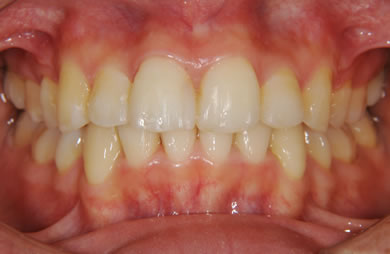

全顎矯正治療+セラミック治療

| 性別/年齢 | 女性 / 26歳 | ||||||||||||||||||||||||||||||||

| 主訴 | 上下乱ぐい歯と出っ歯を治したい。 | ||||||||||||||||||||||||||||||||

| 治療方針 | 口元が出ていていること、がたつきが大きいことより、上下左右の第一小臼歯および親知らずを抜歯し、マルチブラケット治療を行う。抜歯した隙間を活用できるよう上顎にはインプラントアンカー(釘)を使用し、その釘より歯を後ろに移動する。 | ||||||||||||||||||||||||||||||||

| 治療内容 | 唇側矯正(シルバー)、矯正用スピードインプラント、ハイブリッドセラミックインレー2本 | ||||||||||||||||||||||||||||||||

| 総治療費 | 802,700円 | ||||||||||||||||||||||||||||||||

| 治療期間 | 2年3ヶ月 |